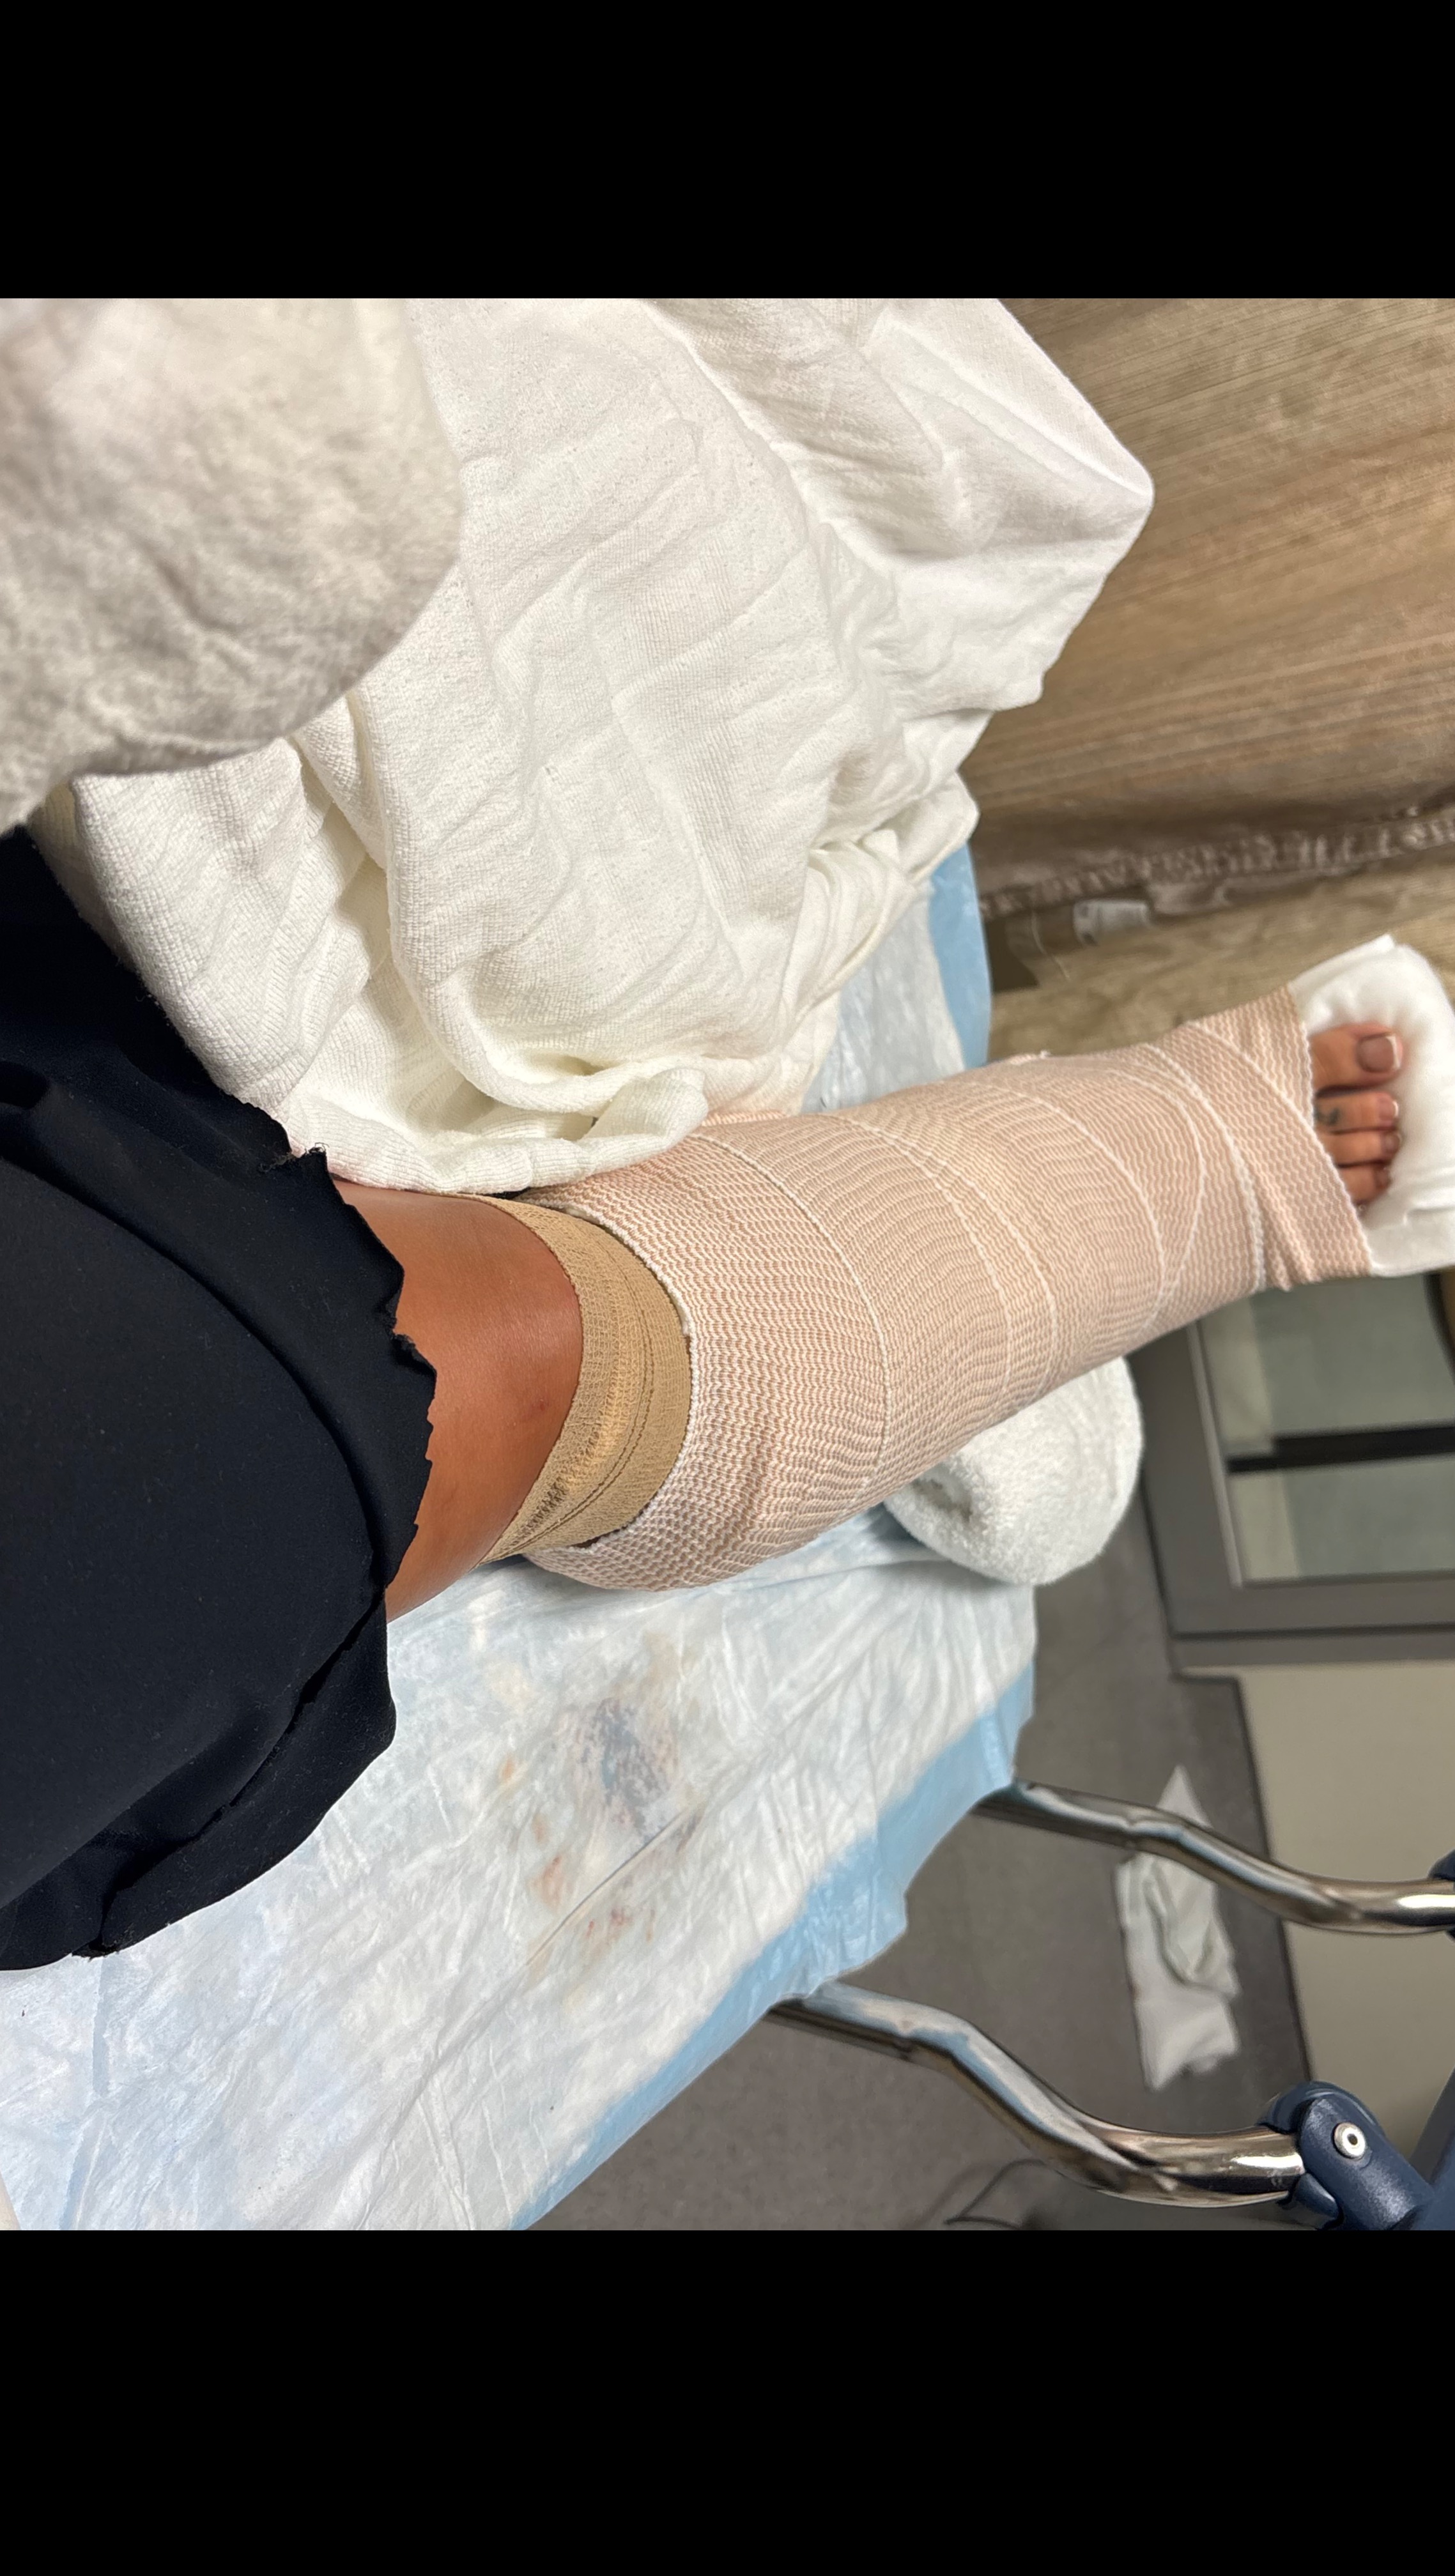

My car was immediately deemed totaled. I had just bought the car with cash only 3 months ago, but that isn’t what I am creating this for. The emts cut my pants because I had a deep to the bone laceration. I had then got into the ambulance and to Halifax I went. I could barely move my right leg especially ankle, was veryyy bruised / swollen. After some x rays what I had hoped was not the case in fact was. Three fractures in my right ankle as well as a fractured patella inside the laceration.. resulting in surgery + 2 screws in my ankle for life + 8 stitches on ankle, 12 stitches on knee and 2 inside knee.

I love love love working at both my jobs so this is a real upsetting time for me as i’m used to clocking in every single day, as well as being a lead bartender at both jobs. I am un able to walk on my own for quite some time with out the walker or crutches. I will have to do physical therapy & get chiropractic care as well.